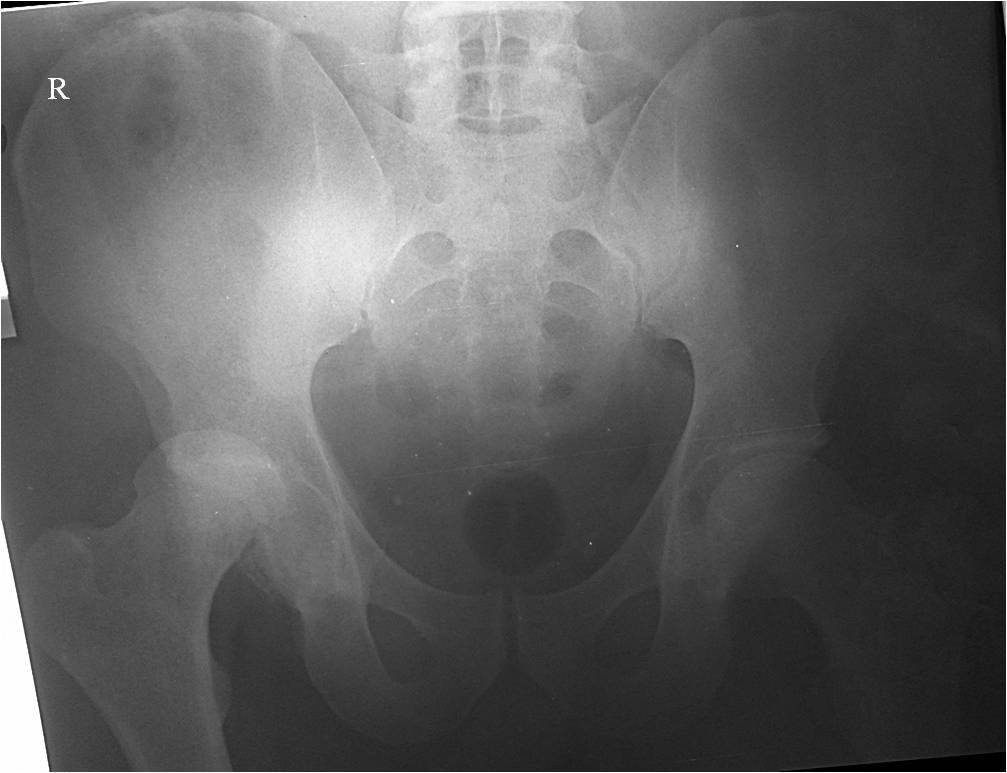

Мужчина, 46 лет, пострадал в результате ДТП (водитель). Удар пришелся

через согнутое правое колено об приборную панель, что привело к заднему

вывиху головки бедра. При госпитализации кроме вывиха бедра

диагностирован перелом нижнего сегмента головки бедра и закрытый перелом

с/3 правого плеча (АО 12-В2).

При поступлении выполнено закрытое вправление головки бедра, налажено

скелетное вытяжение. Контрольный рентген показал разницу в ширине

суставных щелей в сравнении с неповрежденной стороной. Сделали КТ,

которое подтвердило наличие внутрисуставного фрагмента задней стенки

вертлужной впадины и перелом нижне-медиального сегмента головки со

смещением (Pipkin IV).